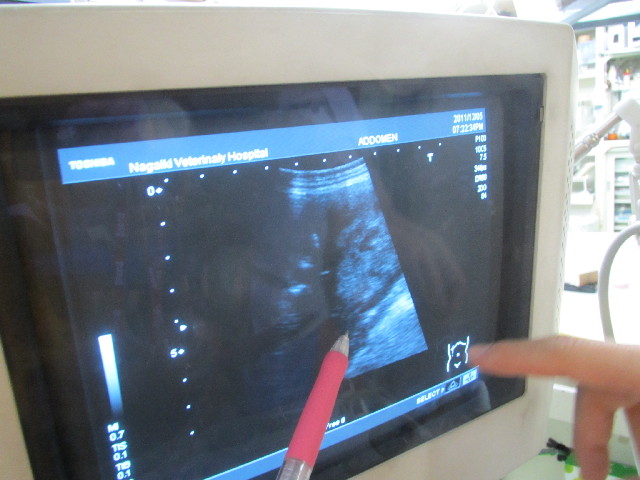

今日は3週間に1度の、べべちゃんの右の腎臓にできてしまった腫瘍(バブちゃん)の大きさをエコーで調べる日でした。

夜間救急でもお世話になったことがあるN先生が図にしてくれました。

前回の院長の見立てのように、腎臓の中から盛り上がってできているのではなく、イボのようにくっついているようです。

なのでべべちゃんの腎臓の機能は正常に保たれているのかもしれません。

腎臓の機能は6割以上が失われてはじめて血液検査の数値異常が出るので、現在100%ちゃんと機能しているとはいいきれませんが、とにかくべべちゃんの腎臓の値は現在いたって正常です★('-^v)

大きさは39×40mmで大きくはなっていないようです(^-^)v

(大きくなると腸管を圧迫したりしてしまったり、転んだ拍子に打って腫瘍が破裂したりして危険)